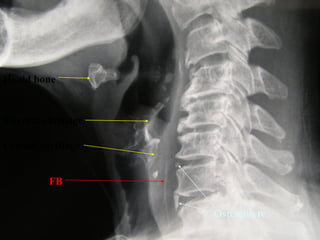

FB Throat - Investigations

Lateral neck XR

FB

Hyoid bone

Thyroid cartilage

Cricoid cartilage

Osteophyte